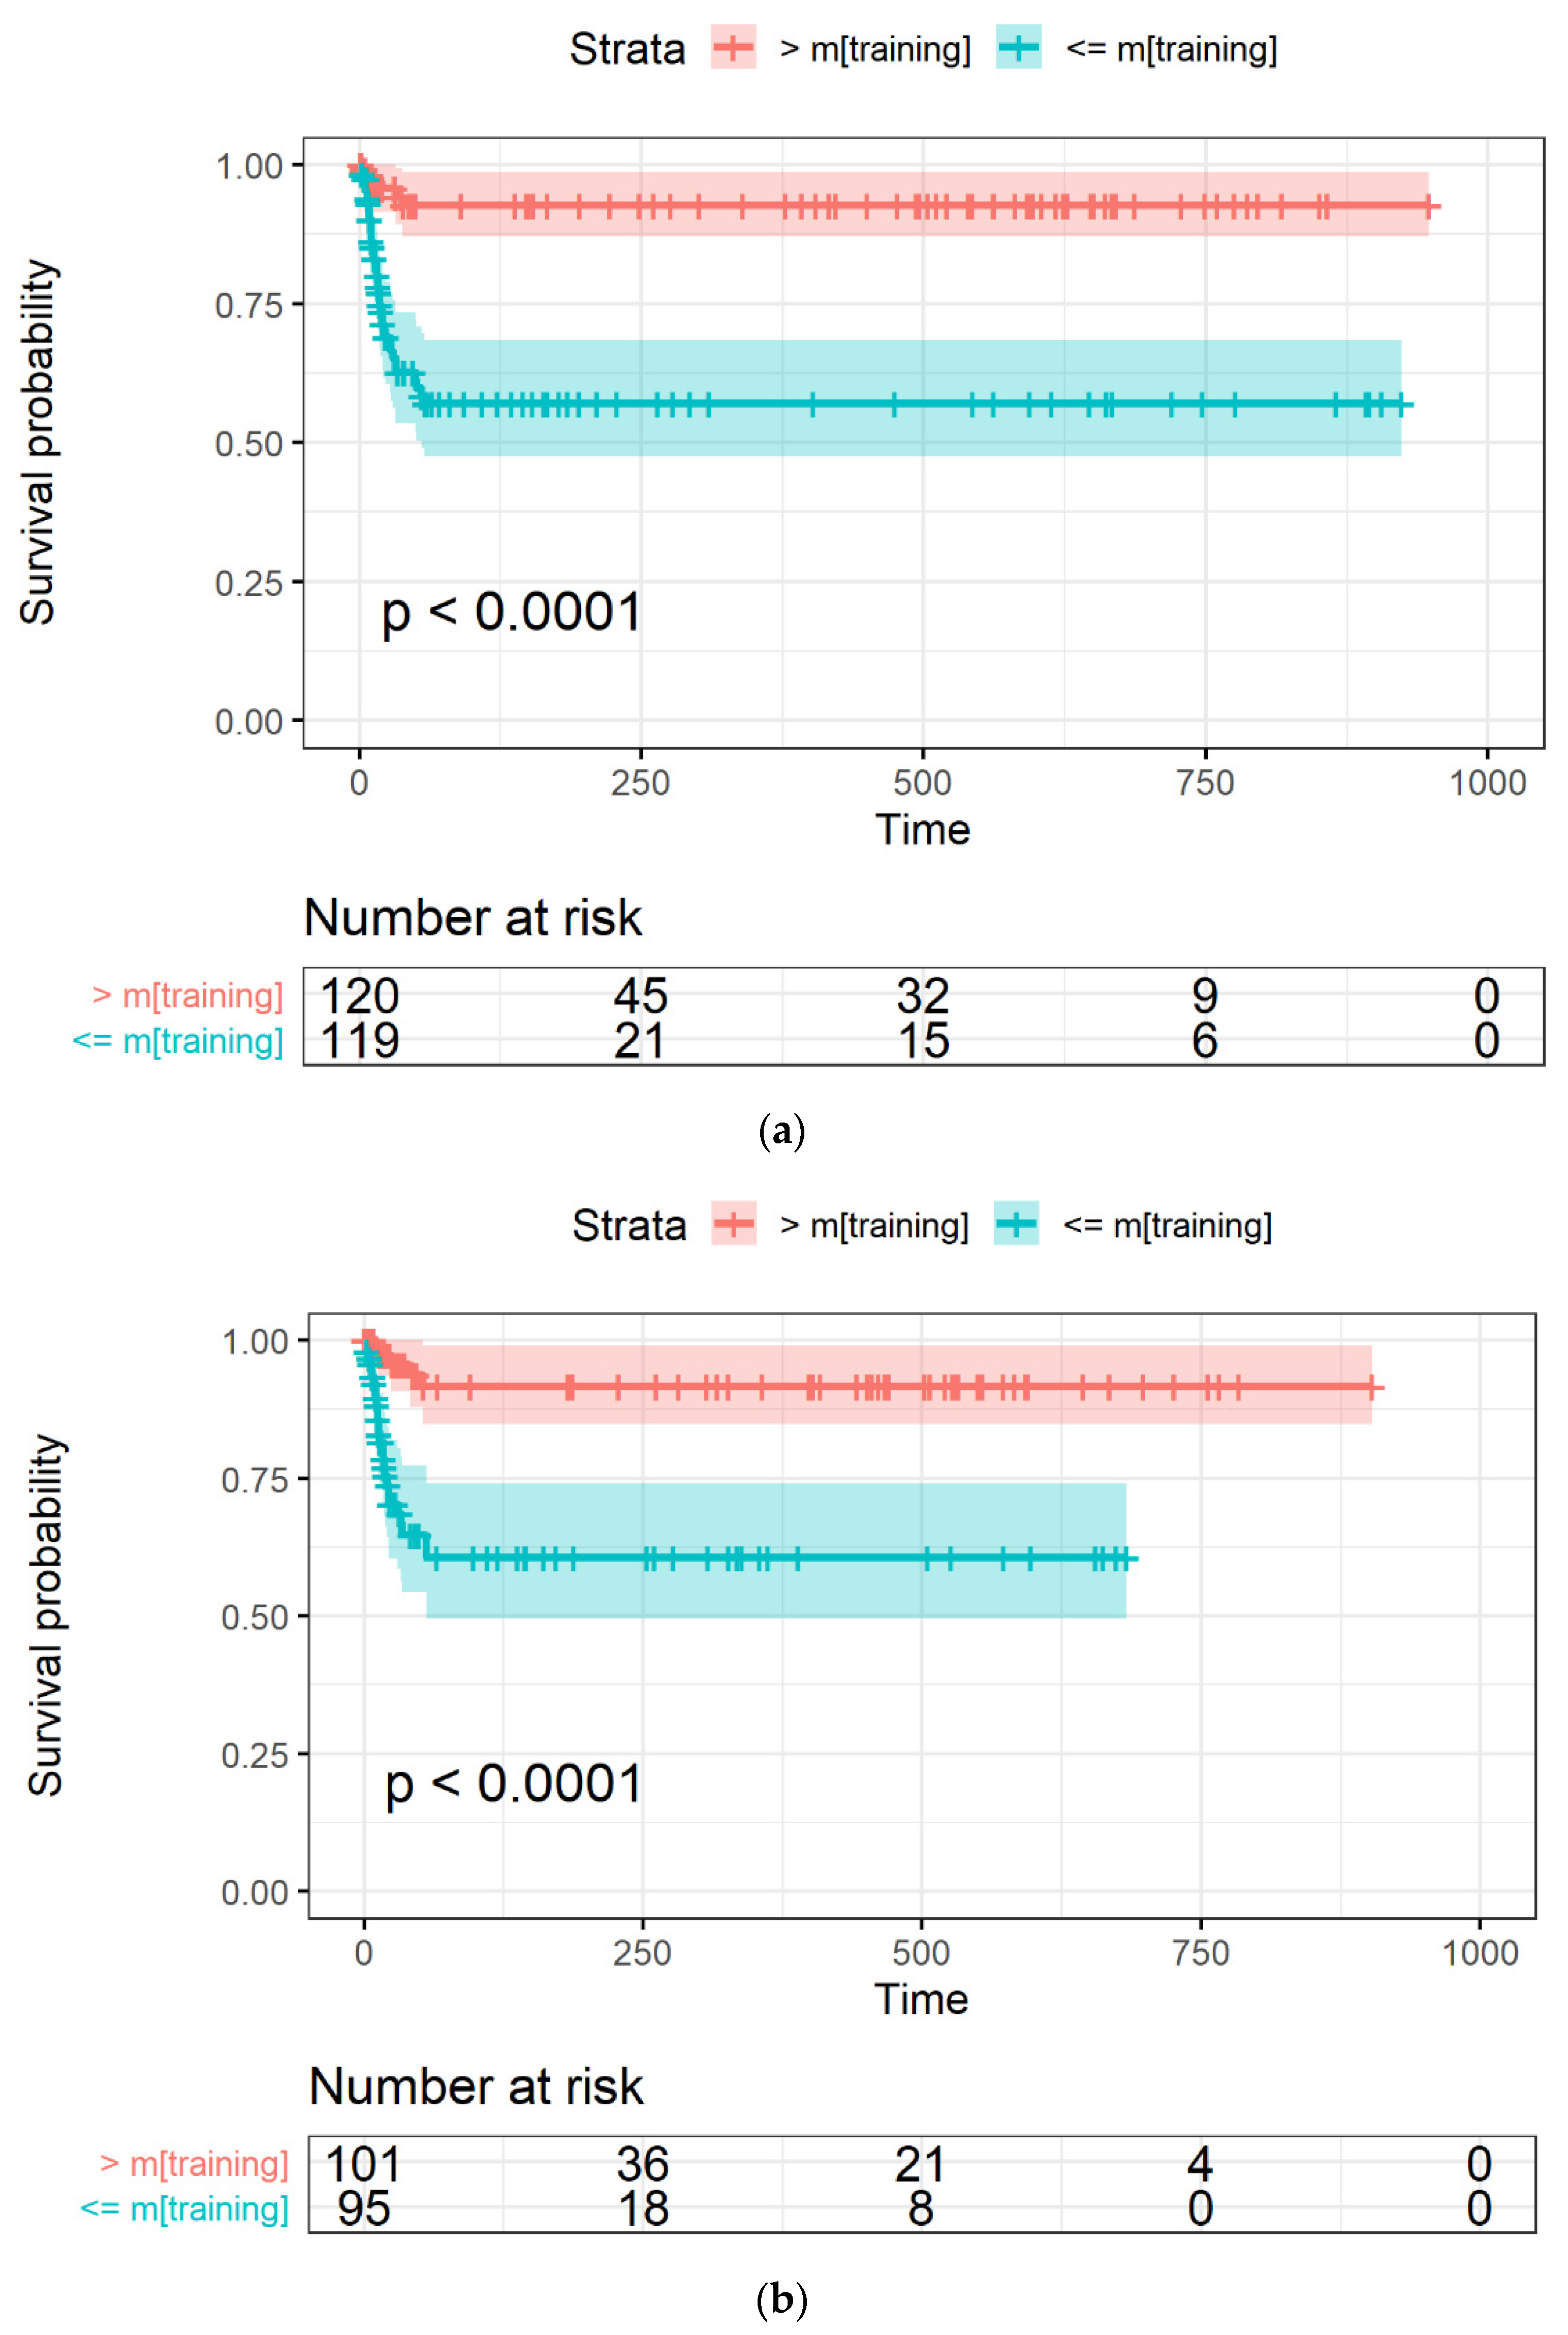

2.3.4. Model Evaluation through Survival Curves

3.3. LASSO-Cox for Feature Selection